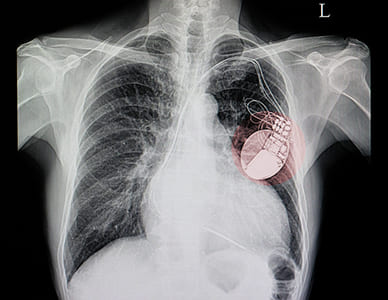

El marcapasos es un pequeño dispositivo operado por pilas que detecta latidos irregulares del corazón y envía señales para mantener un ritmo cardíaco adecuado.

El marcapasos se implanta bajo la piel en un procedimiento que generalmente dura alrededor de una hora. El cardiólogo en Querétaro le administrará un sedante para ayudarlo a relajarse, aunque usted estará despierto durante el procedimiento.